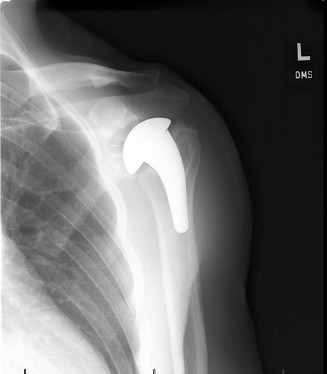

CASE 20 A 72-year-old, right-hand-dominant male with a history of type 2 diabet…

CASE 1 A 76-year-old, right-hand-dominant man presents to clinic complaining of right shoulder pain. The pain…